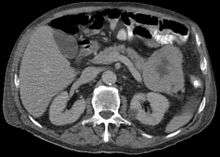

ACC are typically large, up to 10cm, and soft compared to pancreatic adenocarcinoma, lacking its dense stroma. They can arise in any part of the pancreas.[5]